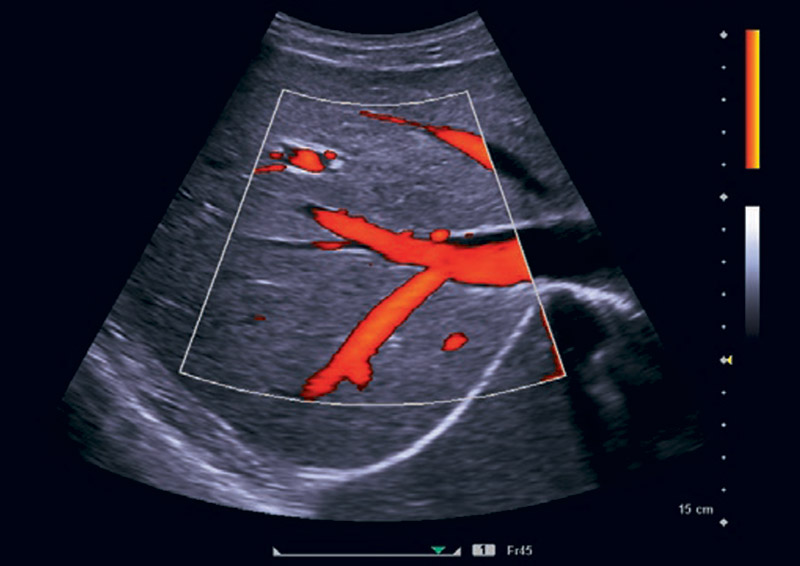

Grazie alla Persistenza Dinamica e all’Auto Flash Suppression, il sistema è in grado di eliminare gli artefatti da movimento nell’utilizzo del color doppler in modo da valorizzare meglio anche i vasi più piccoli